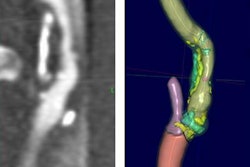

MRI demonstrated findings consistent with acute infarction without microhemorrhages (a, b, and c), along with focal irregular narrowing and banding of the proximal M1 segment of the left middle cerebral artery with a slightly reduced distal flow (d), according to Mirzaee and colleagues. Images courtesy of the RSNA.There are many reasons for stroke in children, ranging from "arterial dissection, embolic or thrombotic stroke, cerebral vasculitis in the context of systemic disease (including Kawasaki disease), and genetic disorders with arteriopathy," Mirzaee and colleagues wrote. Yet their best diagnosis was that the child's stroke had been caused by focal cerebral arteriopathy.